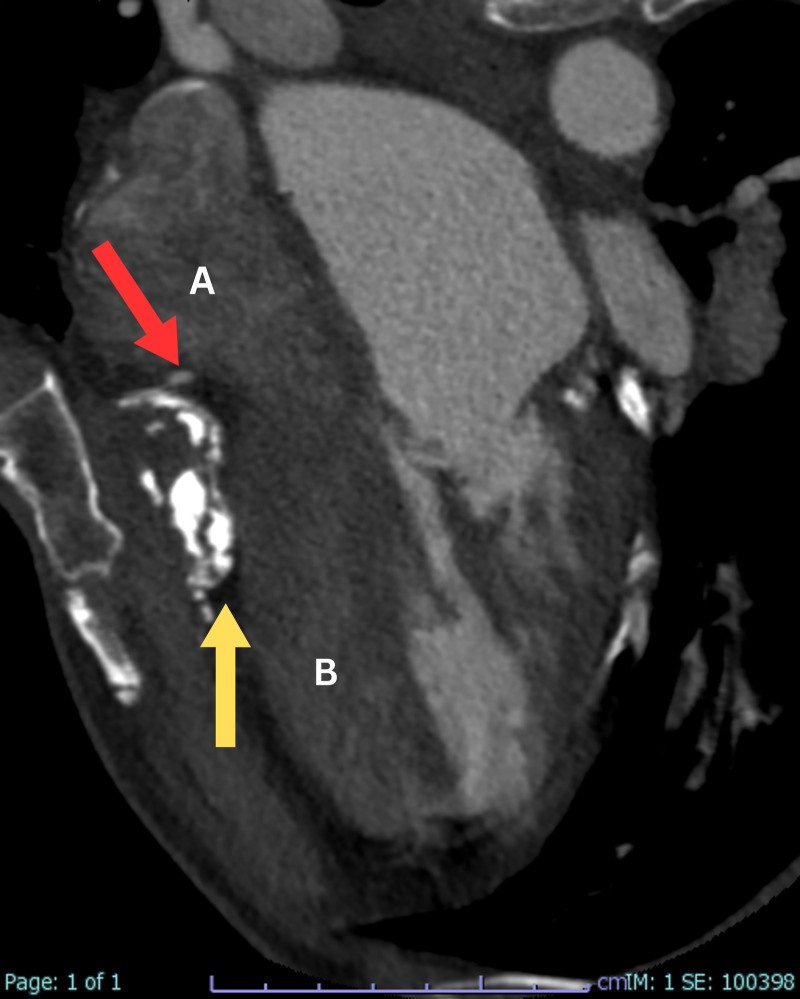

心包切除术后的显像:广泛残留的心包钙化和明显的二尖瓣增厚。

Unveiling Post-Pericardial Resection: Magnificent Imaging of Extensive Residual Pericardial Calcification and Impressive Mitral Valve Thickening.